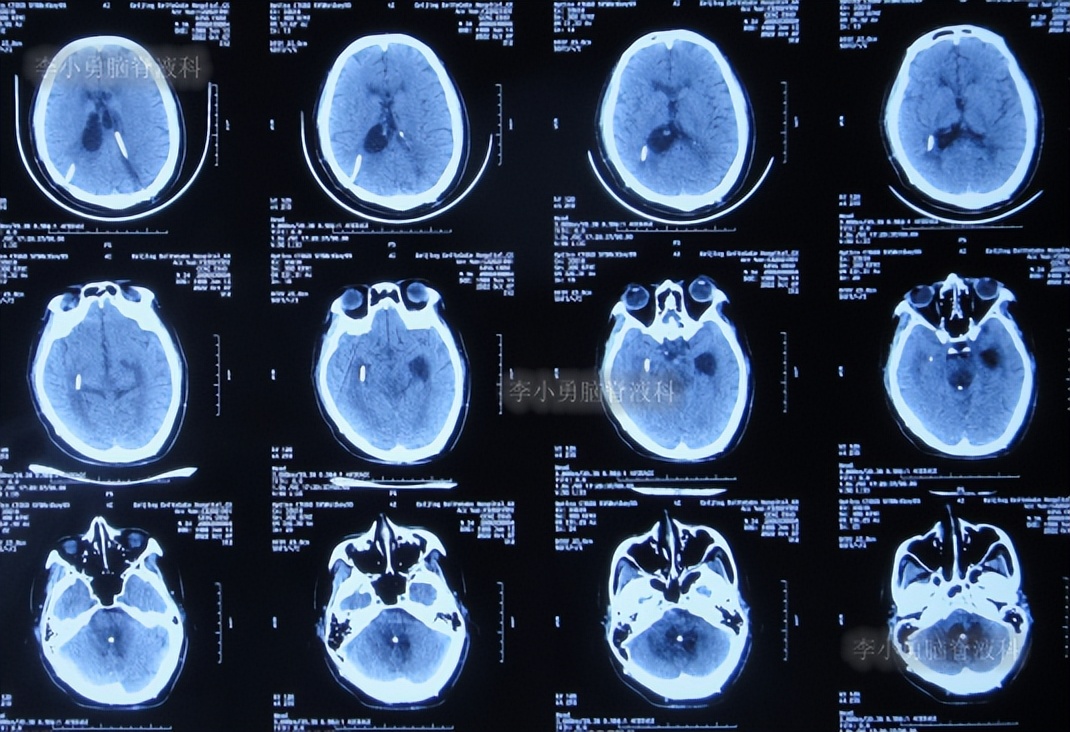

半月后即2022年6月17日,第3次住入李小勇脑脊液科,入院时:进食差,言语混乱,记忆力差,行走差(图-52);查头颅CT示右侧颞角增大,四脑室也稍大(图-53);肺部CT有感染(图-54)。

图-52:2022年6月17 日入院时

图-53:入院时头颅CT

图-54:肺部CT